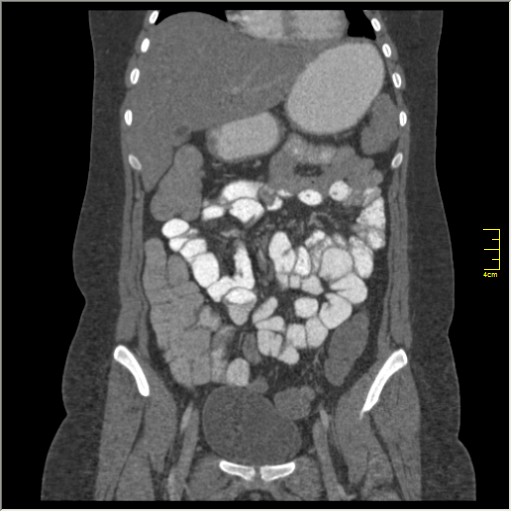

КТ энтерография

Демонстрационные изображение, оцените возможности метода! Толщина среза реконструкции 0.5-1 мм.